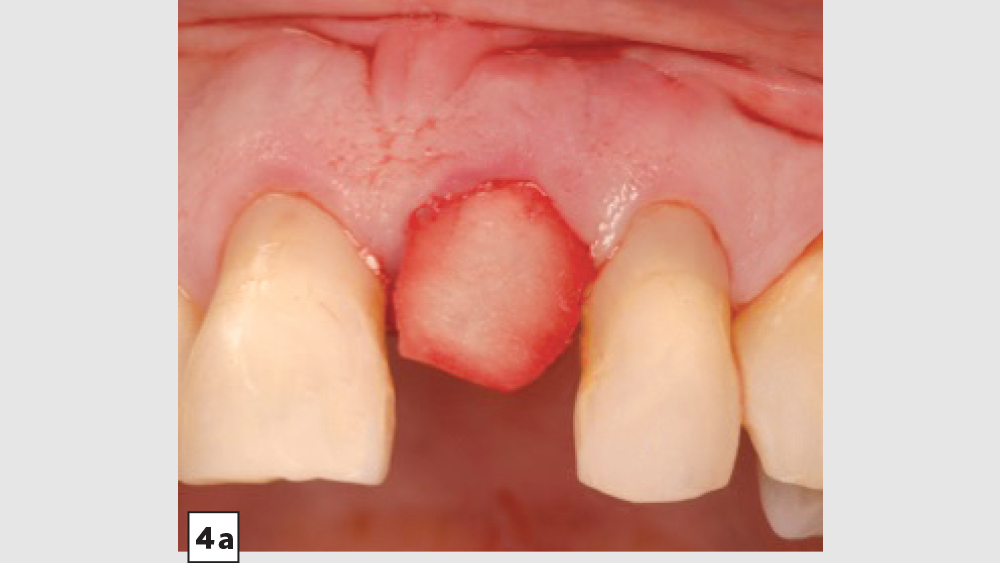

Four-Walled Socket Bone Grafting Technique (Figs. 4a–4d, 5a–5c)

1. Reflection: In most four-walled sockets, a partial mucoperiosteal flap should be reflected to allow for surgical access to the missing buccal plate. This will allow the clinician to place a membrane properly along the buccal plate.

2. Preparation: Ensure there are no soft-tissue remnants within the socket and that bleeding is present. If bleeding is not present, the remaining walls should be decorticated. Care should be exercised around adjacent teeth or vital structures. Bleeding will facilitate early vascularization and initiate the healing process.

3. Graft Material: The graft material (e.g., Newport Biologics Mineralized Cortico/Cancellous Allograft Blend) should be hydrated with sterile saline (0.9% sodium chloride) or platelet-rich fibrin and then gently condensed into the socket. Only small increments of material should be entered into the socket at a time, and a bone-packing instrument should be utilized to condense the bone graft material to avoid air spaces. Usually, when “push-back” of the material is present, the material is packed sufficiently. Care should be exercised to avoid packing the graft material too densely, as this may displace the membrane, interfere with angiogenesis and delay the healing process.

4. Membrane: Because of the missing buccal plate, a longer-acting collagen cross-linked membrane (e.g., Newport Biologics Resorbable Collagen Membrane 3-4) or a PTFE (e.g., CytoSurg Non-Resorbable PTFE Membrane) should be used. The membrane should be trimmed in a modified V-shape (Fig. 5a).6 The narrower part of the membrane should encompass the entire missing buccal wall. Placement of the membrane should be within the confines of the socket, as extending the membrane over the external aspect of any remaining buccal wall will compromise the blood supply. The membrane should cover only the missing buccal wall; the other walls should not have membrane coverage, as this will decrease the healing of the socket. The goal of the membrane is to prevent the soft tissue from repopulating the defect. The wider part of the membrane should be trimmed so that it is slightly larger than the socket opening to allow for placement under the flap.

5. Closure: Closure should be completed with a 3-0 or 4-0 high-tensile suture material (e.g., PGA or PTFE) with a crisscross suture technique. Care should be exercised to avoid suturing through the membrane. Gut sutures (plain, chromic) should be avoided, as they have a compromised tensile strength and incision line breakdown may occur.